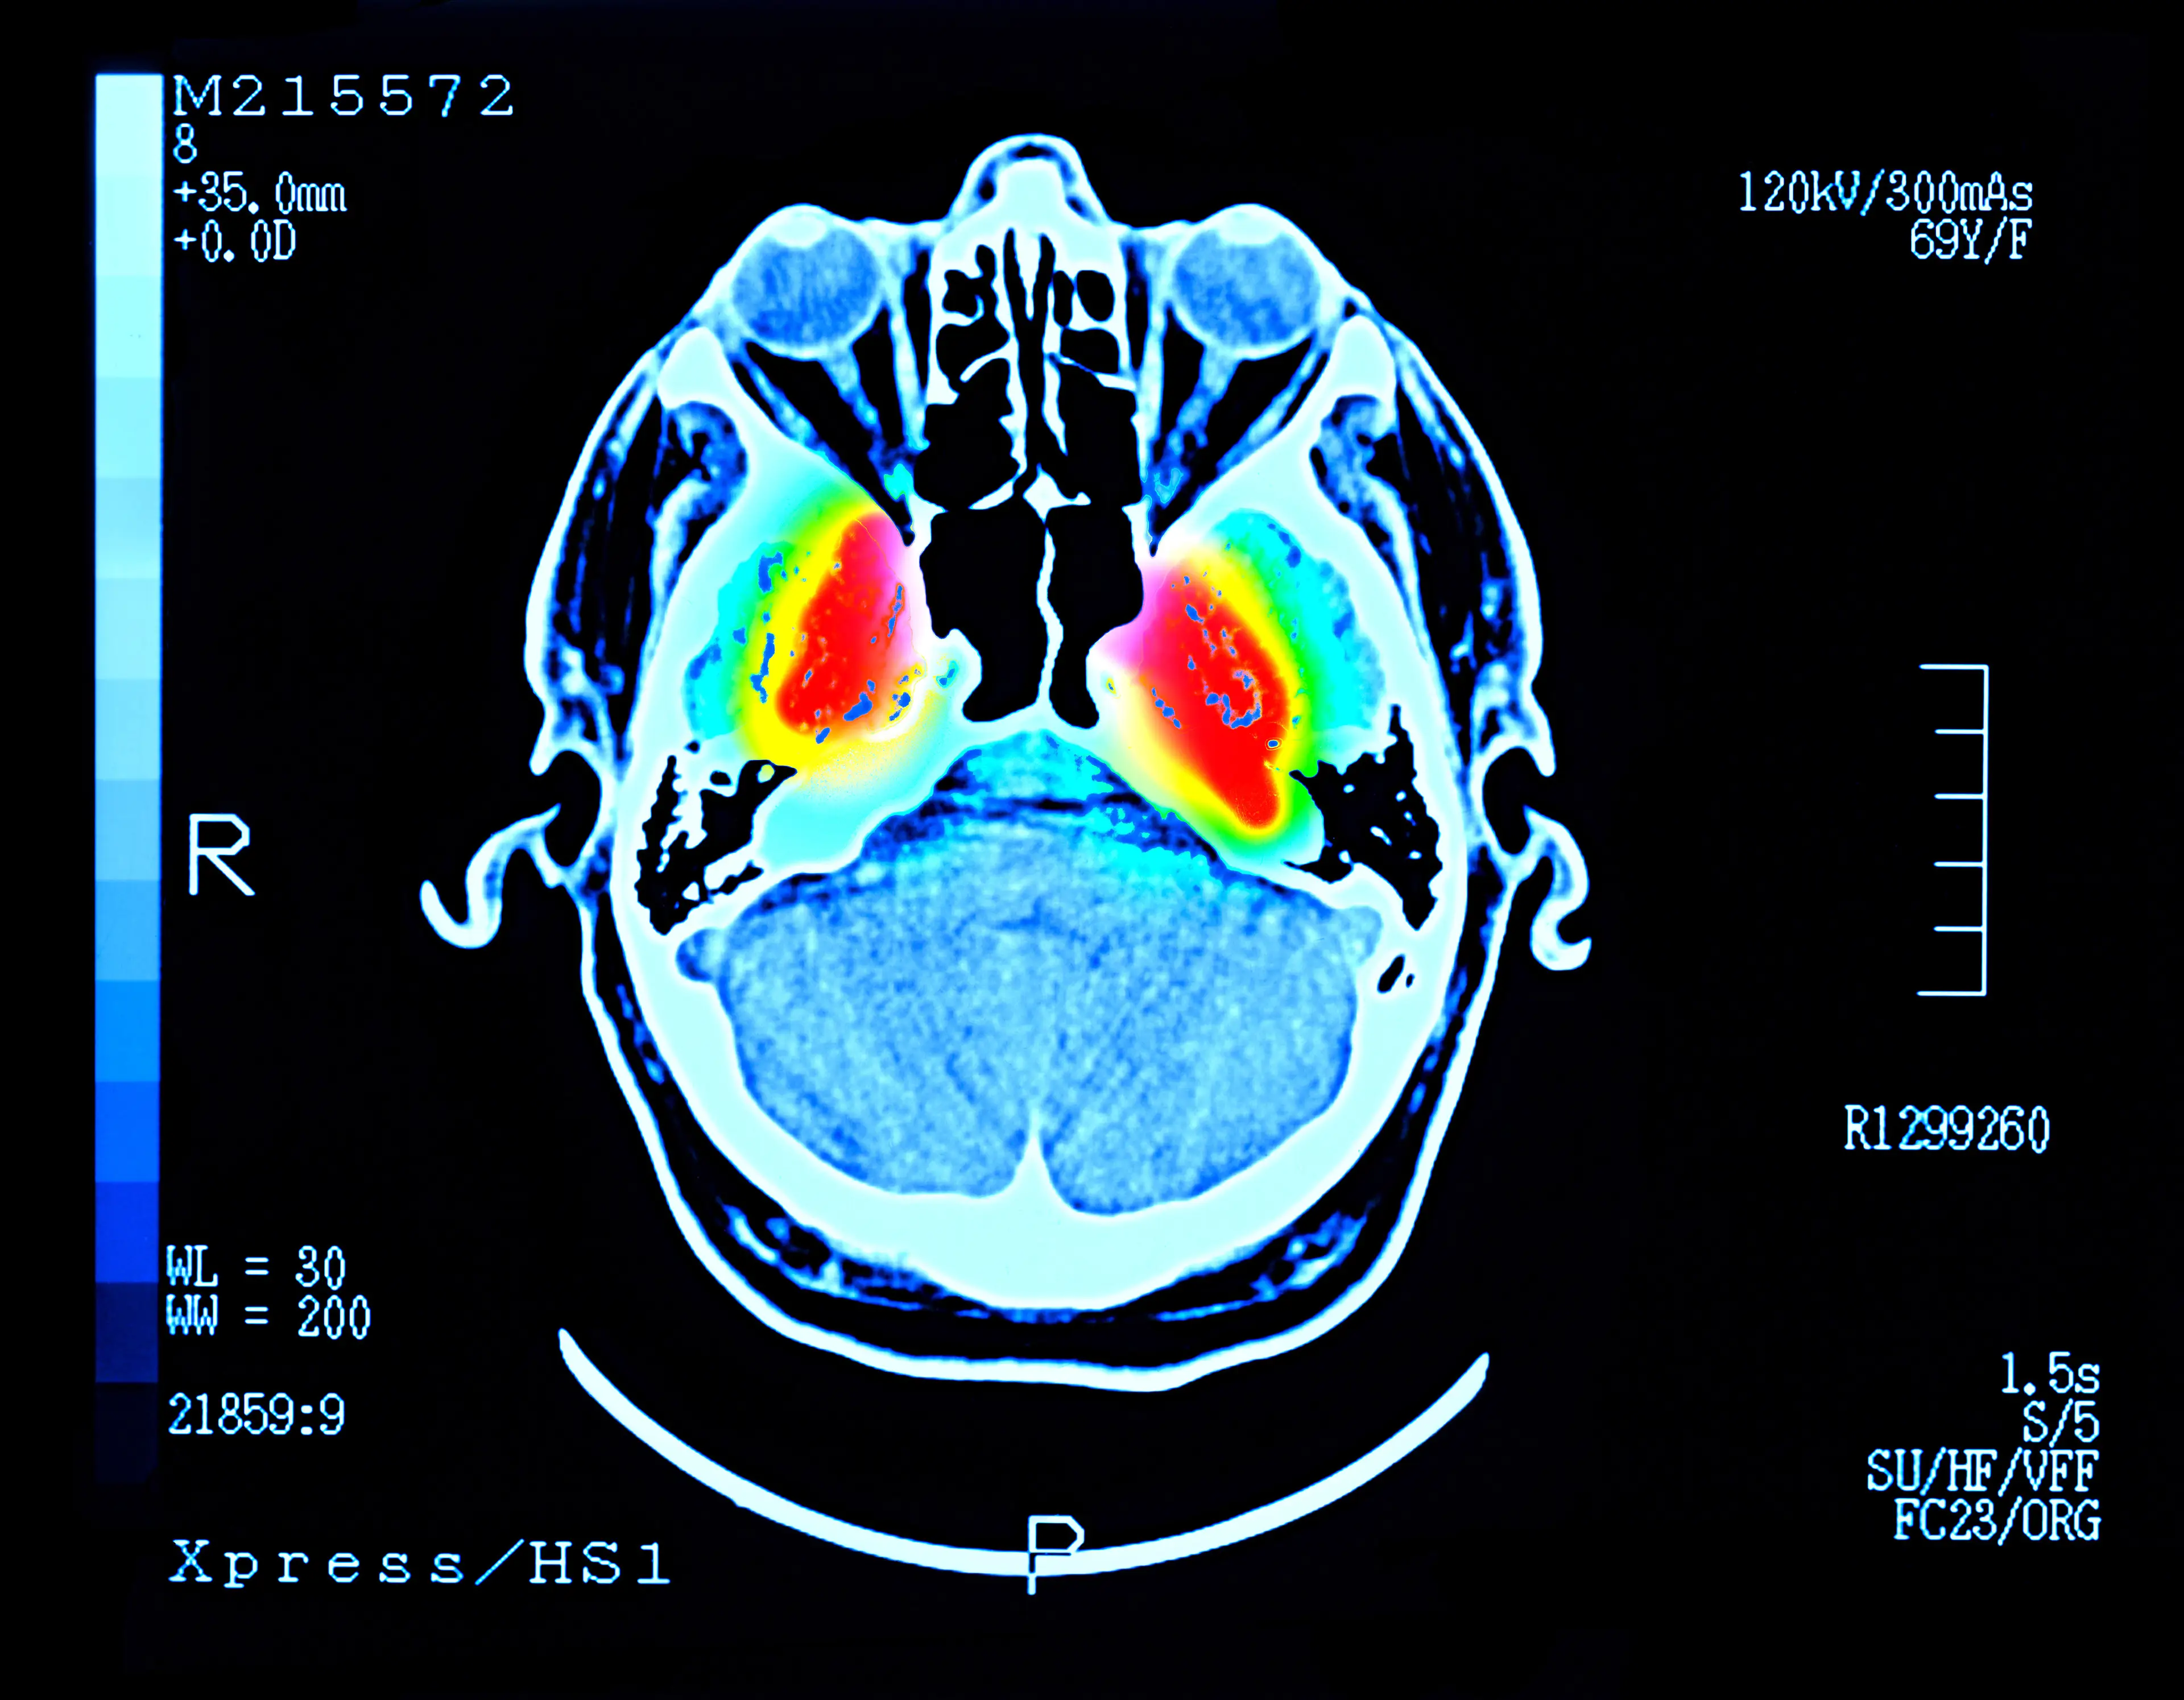

A leader of research in this arena is Dr Daniel Amen, who has conducted a multitude of scans aimed at measuring brain flow and activity.

"From a brain imaging perspective, marijuana use is consistently associated with measurable changes in brain function," he recently told The Post.

"Marijuana users demonstrate widespread reductions in cerebral blood flow, particularly in regions critical for memory, coordination, emotion and executive function," Dr Amen added, pointing out that THC within marijuana is the major culprit in these cases.

This psychoactive compound wreaks havoc on the brain's cerebellum and basal ganglia, which are responsible for balance and staying upright.

Referring to prolonged blood flow reduction to this area of the brain, he explained: "Cannabis users show significant hippocampal hypoperfusion, with studies demonstrating reductions of up to 13–17% compared to controls."

"This is clinically meaningful because the hippocampus is highly vulnerable to neurodegenerative processes and is essential for learning and memory consolidation."

The area of the brain responsible for impulse control, decision making and opinion forming is the pre-frontal cortex, which Dr Amen says scans have shown to be impacted by long-term cannabis inhalation.

Like in the above instance, a person's ability to plan, organise, concentrate and multitask comes from the prefrontal cortex, which is damaged by THC over long periods of marijuana use.

According to Dr Amen, in many long-term cannabis inhalation cases, decreased activity in this area was observed during imaging studies.

"This may contribute to emotional blunting in some individuals, but cannabis use is also associated with increased rates of anxiety, paranoia and psychosis, particularly in high-frequency users or those with genetic vulnerability," he continued.

"Findings suggest that marijuana use is associated with global reductions in brain function, rather than enhancement," Dr Amen continued.

"While some individuals report short-term benefits, imaging data indicate potential negative effects on memory, coordination, emotional regulation and executive function - especially with chronic or heavy use."